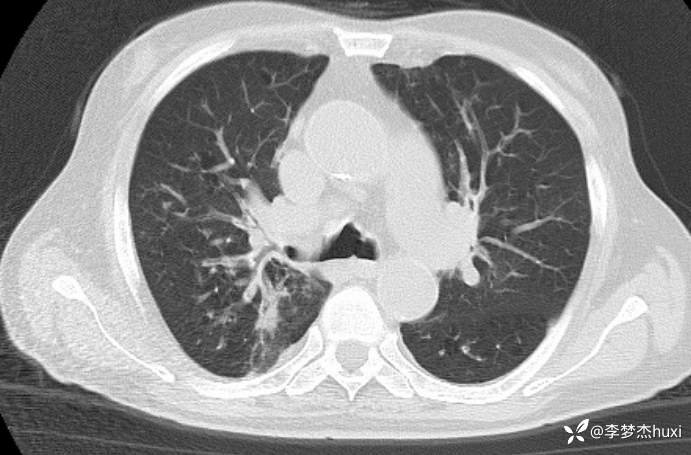

男, 82 岁,主因慢性咳喘20余年,患慢阻肺,平时喘息药物维持,半年前反复住院,并因为病重转上级医院治疗,自诉回家后做梦梦到自己换了一个狗肺,感觉从此不再喘息。